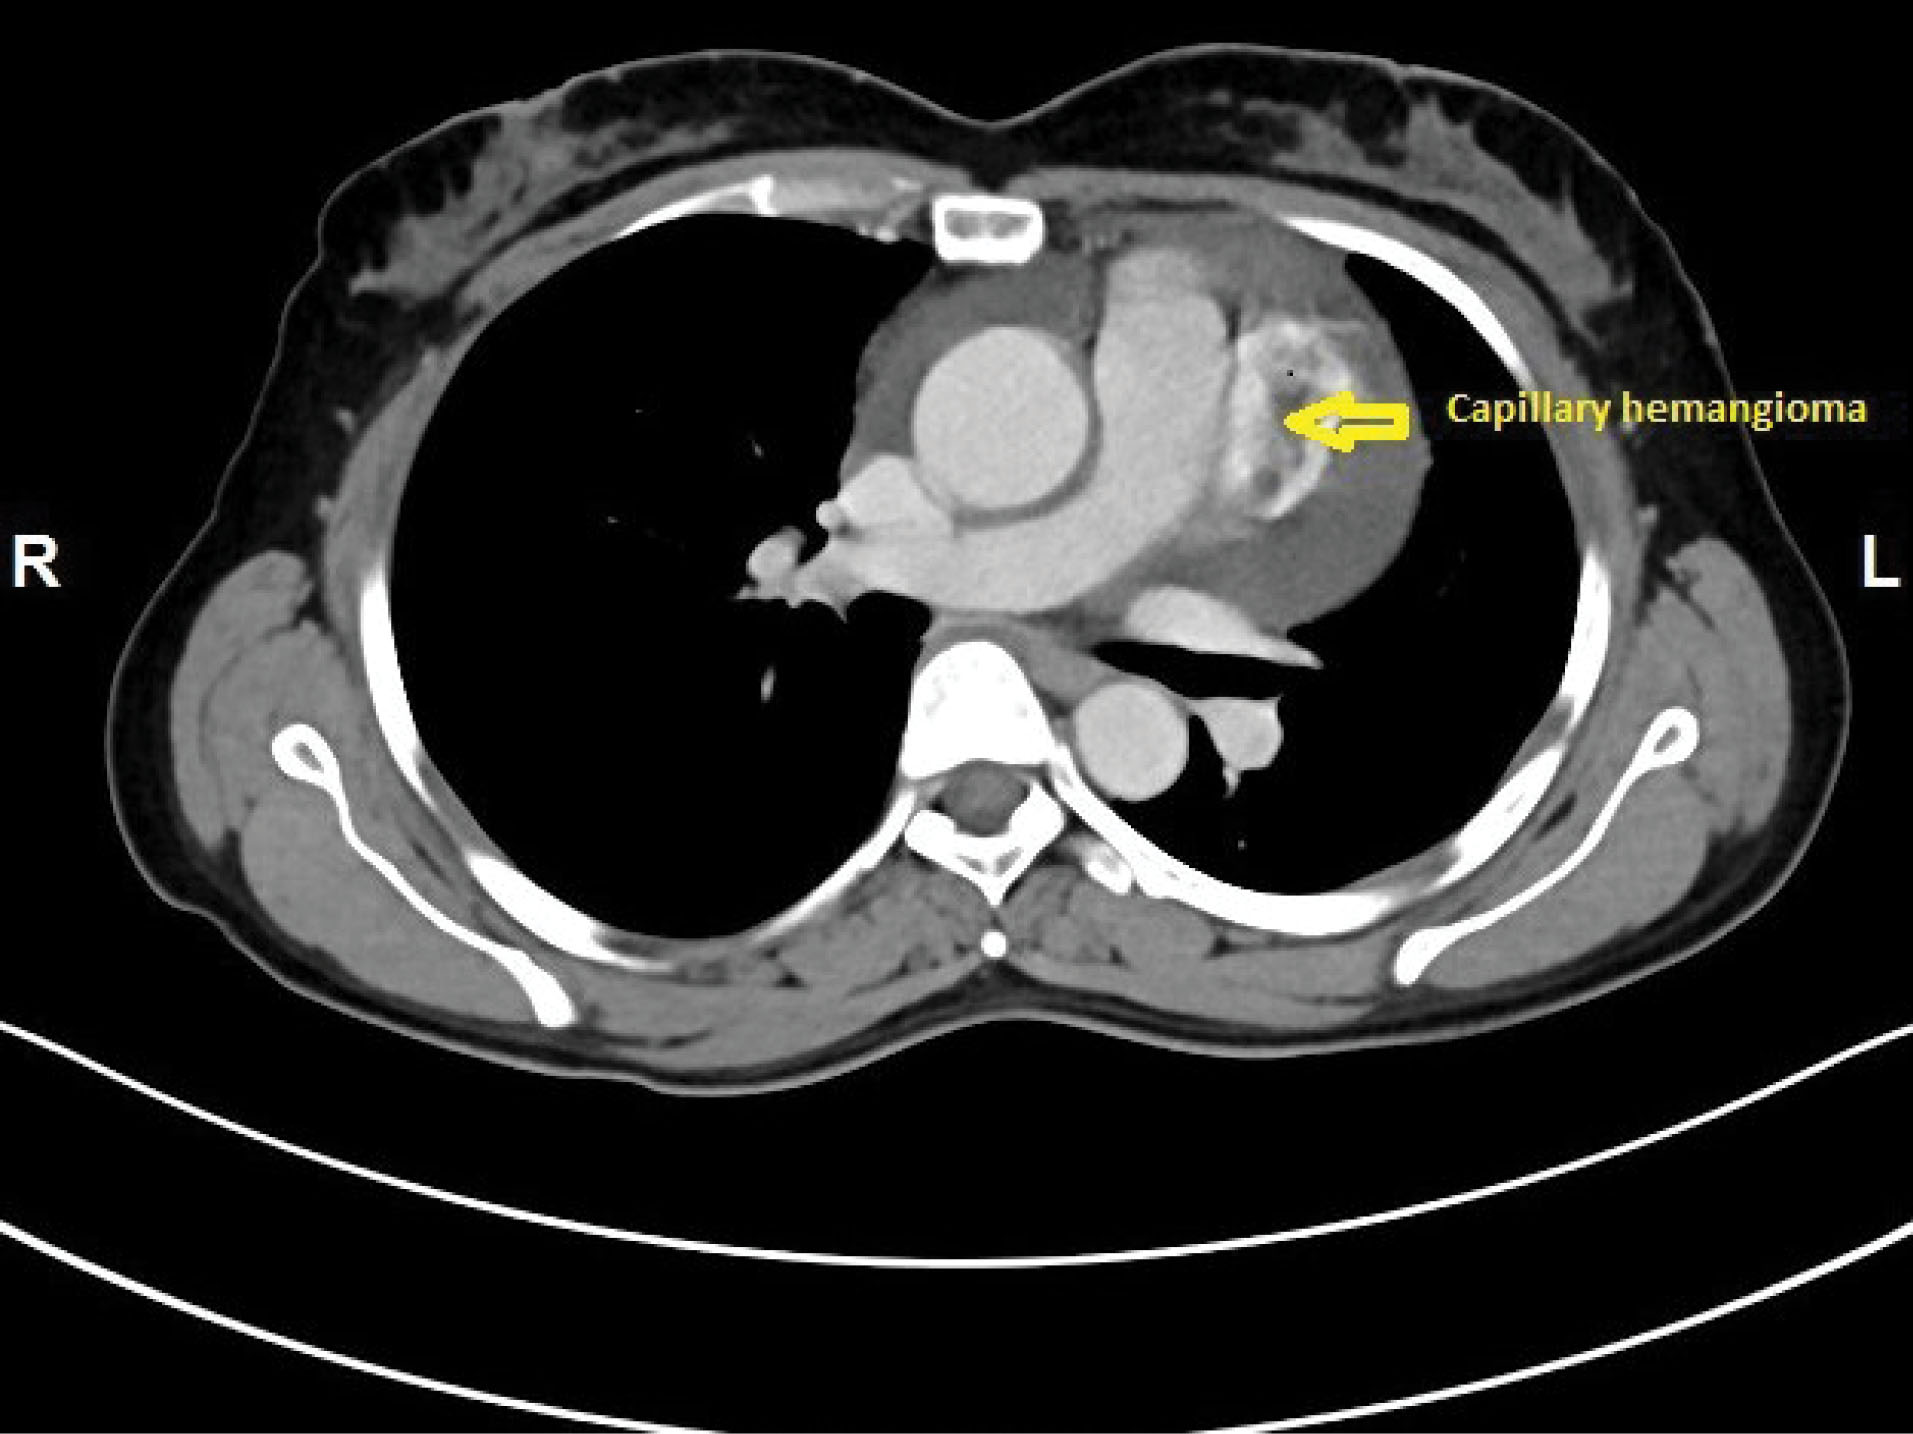

A 48-year-old female was admitted with history of breathlessness since 3 months. On exploring clinical history, it was found that she also had recurrent history of giddiness on and off with mild chest discomfort since 6 months. She was non diabetic and normotensive. General clinical examination and cardiovascular examination was unremarkable. Initial 2-D Transthoracic Echocardiography revealed large pericardial effusion with mild Pulmonary arterial hypertension without any other valvular, cardiac chamber or flow abnormality. She underwent echo guided pericardiocentesis for diagnostic and therapeutic purposes and initially 650 ml of straw coloured, slightly turbid fluid was drained. The pericardial fluid examination revealed exudative fluid but Lactate dehydrogenase (LDH), Adenosine Deaminase (ADA) test reports were within normal limits. Gram staining and Ziehl-Neelsen staining for Acid fast bacilli were negative. The cytological examination of fluid showed mesothelial cells and inflammatory cells in haemorrhagic background but without any malignant cells. Antinuclear antibodies and Anti-double stranded DNA antibodies were also found to be negative. Haematological and routine biochemical tests are also within normal limits. Since all the tests were negative she was labelled as idiopathic pericardial effusion and kept under medical supervision with diuretics and low dose steroids. After one month, she again developed moderate pericardial effusion with recurrence of symptoms. She was planned for Pericardial window formation. We started further investigations. CECT thorax revealed well defined middle mediastinal mass of 43 x30 mm superior to left ventricle and posterolateral to main pulmonary artery infundibulum without any compression ( and 2). PET scan showed, heterogeneous enhancing exophytic, moderately hypermetabolic heterogeneous mass lesion posterolateral to main pulmonary trunk and anterior to the left ventricle with SUV Max of 4.0 and no other evidence of hypermetabolic lesion elsewhere in thoracic cavity.

jcvtr-13-250-g001

Figure 1. Contrast enhanced computed tomography axial plane view showing a relatively heterogeneous capillary haemangioma mass (48 × 30 mm) marked by arrow, posterolateral to main pulmonary artery infundibulum.